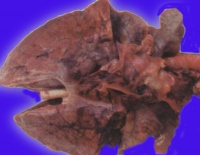

肺表面苍白,含水量增多,切面有大量液体渗出。显微镜下观察,可将其分为间质期,肺泡壁期和肺泡期。

间质期是肺水肿的最早表现,液体局限在肺泡外血管和传导气道周围的疏松结缔组织中,支气管、血管周围腔隙和叶间隔增宽,淋巴管扩张。液体进一步潴留时,进入肺泡壁期。液体蓄积在厚的肺泡毛细血管膜一侧,肺泡壁进行性增厚。发展到肺泡期时,可见充满液体的肺泡壁丧失了环形结构,出现褶皱。无论是微血管内压力增高还是通透性增加引起的肺水肿,肺泡腔内液体的蛋白均与肺间质内相同,提示表面活性物质破坏,而且上皮丧失了滤网能力。